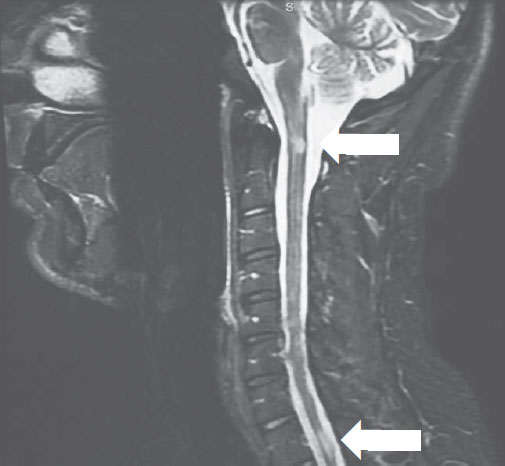

Оньека (имя героини и некоторые обстоятельства ее жизни изменены в целях защиты личных данных) меняется в лице, когда я показываю ей снимки магнитно-резонансной томографии, МРТ (рис. 1.1, 1.2).

РИСУНОК 1.2. ШЕЙНЫЙ ОТДЕЛ ПОЗВОНОЧНИКА ОНЬЕКИ, СНИМОК МРТ В РЕЖИМЕ T2-STIR, САГИТТАЛЬНАЯ ПРОЕКЦИЯ. ОЧАГИ РАССЕЯННОГО СКЛЕРОЗА ОТМЕЧЕНЫ СТРЕЛКАМИ

Магнитно-резонансная томография дает возможность диагностировать РС и отслеживать его течение, позволяя прижизненно видеть очаги поражения (видимые области повреждения нервной ткани) в живом организме. Очаги при РС выглядят яркими пятнами на Т2-взвешенных изображениях, а при стойкой утрате нервных волокон – темными («черные дыры») на Т1-взвешенных изображениях. Активный очаг заболевания вызывает временное нарушение функций гематоэнцефалического барьера (барьера между кровеносной и центральной нервной системами), и вводимый перед исследованием гадолиний-содержащий контраст проникает в очаг, «подсвечивая» его на снимке. В результате таких повреждений головной мозг частично атрофируется (уменьшается в размерах) примерно на 0,5–1,35 % в год [3]. Для мониторинга РС проводятся регулярные осмотры и периодический МРТ-сканинг, поскольку новые очаги часто появляются бессимптомно.